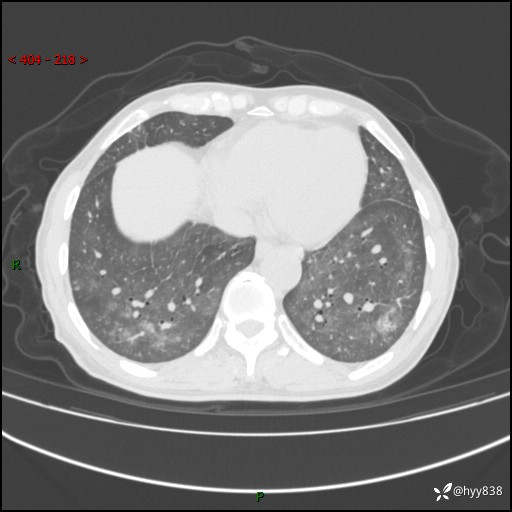

辅助检查:CT

胸部CT平扫

不是讨论肺部结节